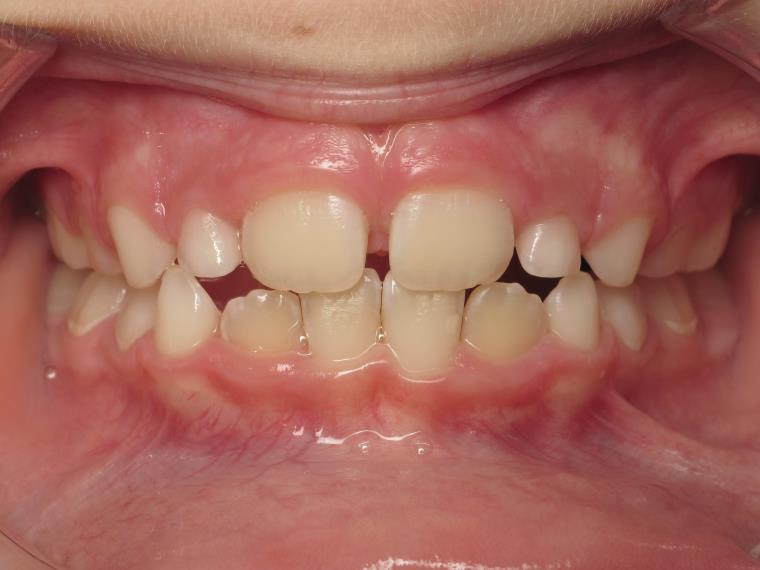

6 décalage sagittal 5 ans

Décalage entre les dents d avant en arrière

bilan début fin de traitement